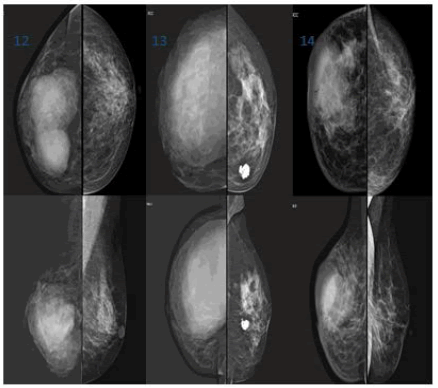

12. Case 13-15: NHL/Phylloides/Metastasis (Figure 17).

Figure 17. Case 12: Lymphoma.Well circumscribed lobulated dense mass lesion with obscured margins in the inner lower quadrant of right breast, non-calcified and node-negative; Case 13: Malignant phyllodes. Large well-circumscribed dense probably cystic mass lesion noted in upper outer quadrant involving almost entire right breast-sparing the inner quadrant (on USG large complex cyst with a solid component) and left breast showing popcorn calcification/involuting calcified fibroadenoma; Case 14: Metastatic DCC. Irregular/ill-defined dense mass lesion with obscured margins in upper outer quadrant of the right breast with, associated features like skin thickening and nipple retraction. Node negative mass with micro-calcifications which are pleomorphic